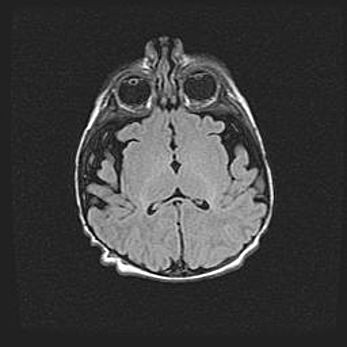

Сообщающаяся гидроцефалия. Кистозная энцефаломаляция головного мозга.

Возраст: 3 месяца 4 дня

Вес: 3100 г

Пол: женский

Окружность головы: 34 см

Срок гестации: 31 неделя

Кистозная энцефаломаляция головного мозга - одна из форм поражения головного мозга в детском возрасте. Характеризуется возникновением множественных и распространённых кист в коре, белом веществе и подкорковых образованиях головного мозга у плодов, новорождённых и детей раннего возраста. Развитие кистозной энцефаломаляции связано с внутриутробной асфиксией и гипотонией, родовой травмой, тромбозом синусов, пороками развития сосудов, инфекциями, сепсисом и другими причинами. Наиболее значимые инфекционные агенты: вирусы простого герпеса, цитомегалии, краснухи, токсоплазмы, энтеробактерии, золотистый стафилококк и другие.